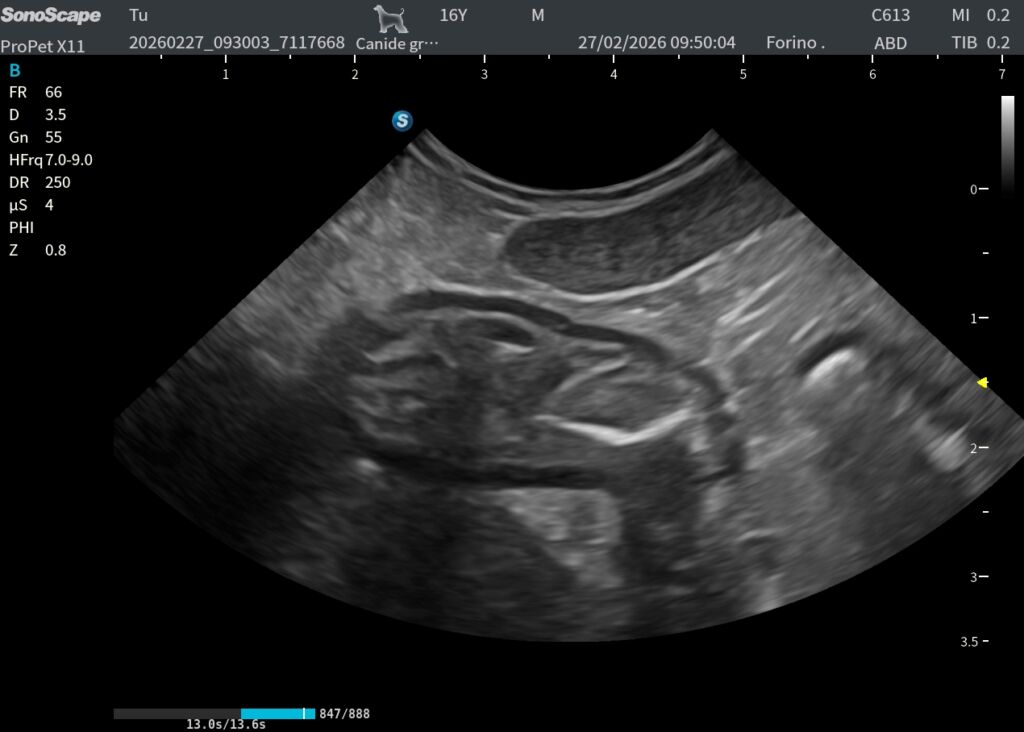

Pratica su cani vivi

Uno dei punti chiave del corso è la possibilità di esercitarsi su cani vivi, così da imparare la vera manualità.

Eco 5

Eco 4

Eco 3